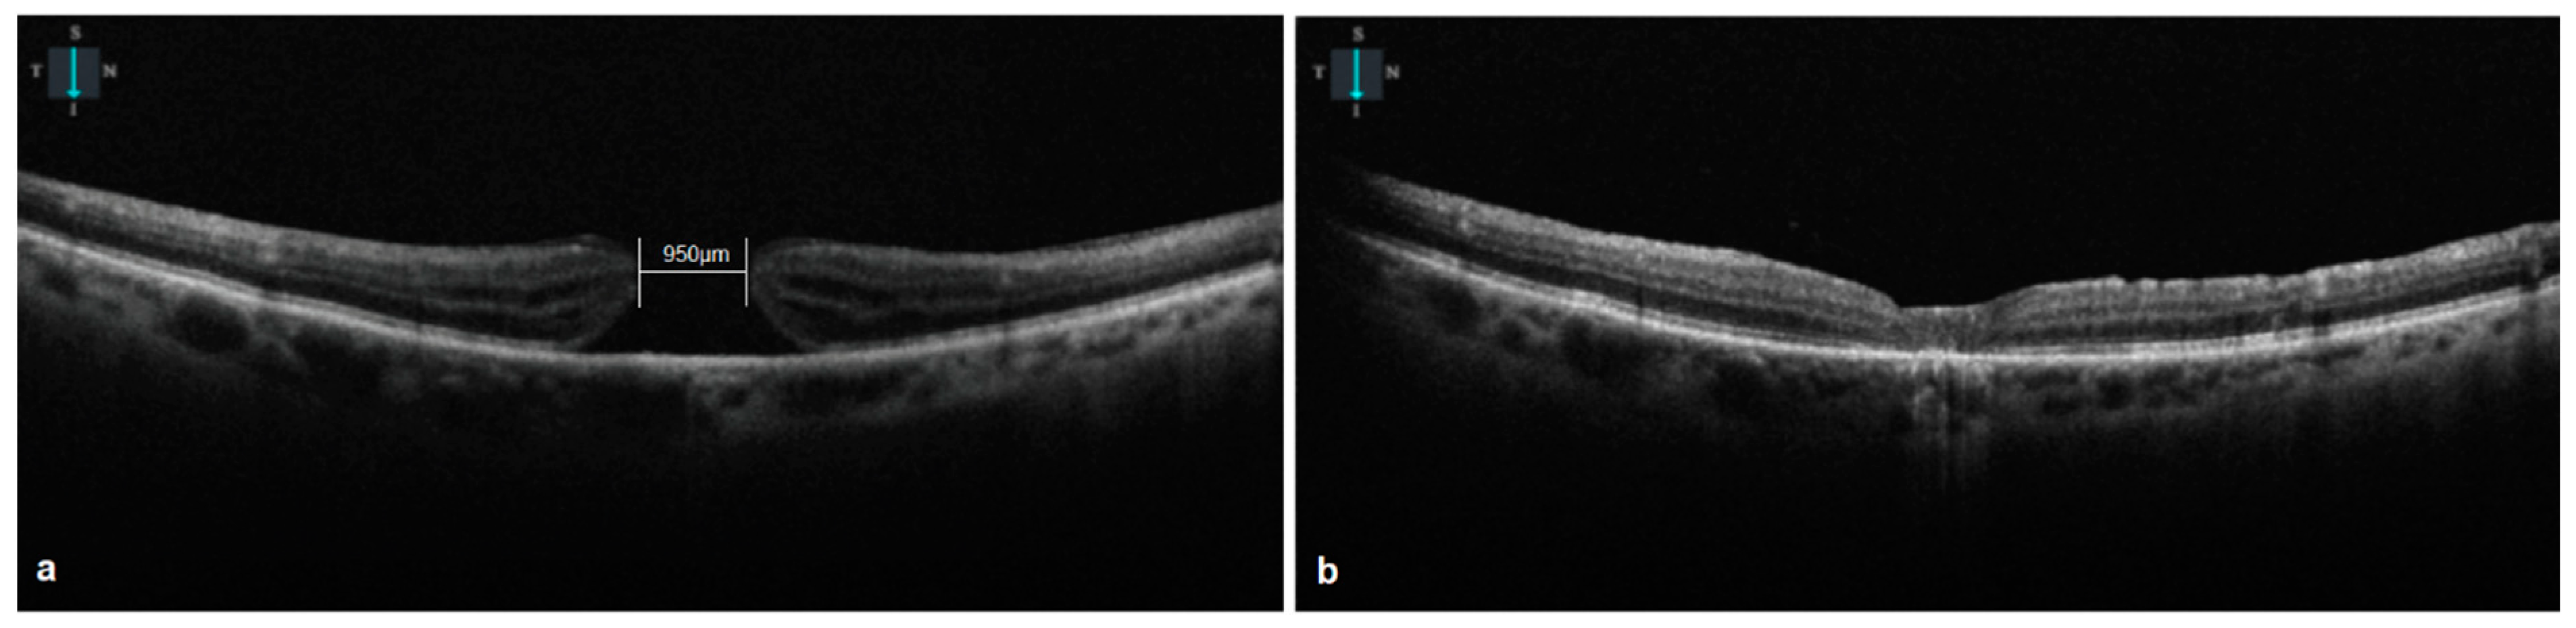

- All the macular holes closed postoperatively (Figure 1). Visual acuity improved to 0.51 ± 0.20 logMAR (p = 0.01 < 0.05) at 6 weeks and to 0.45 ± 0.25 (p = 0.008 < 0.05) at the final follow-up visit. The external limiting membrane (ELM) was continuous in six eyes (37.5%) at 6 weeks postoperatively. At the final follow-up visit, the ellipsoid zone was disrupted in all of the eyes. The closure pattern was 1A for 6 cases (Figure 2) and 1C for 10 cases (Figure 1) at the final follow-up [14]. Table 3 summarizes the surgical outcomes.